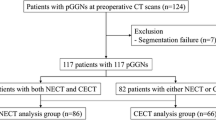

Our study population comprised 104 consecutive patients who underwent preoperative non-enhanced CT using a SSN evaluation protocol and subsequent surgical resection between November 2014 and July 2016. Among the 104 patients, three patients whose pathological diagnoses did not belong to the adenocarcinoma spectrum including precursors (atypical adenomatous hyperplasia (AAH), AIS, MIA and IPA) were excluded. Seven additional patients were excluded owing to semi-automatic segmentation failure. In addition, five patients in whom nodules were classified as solid by at least one reader (E.J.H. and H.K. with 6 and 7 years of experience in chest CT, respectively), were also excluded. Consequently, 89 patients (39 men and 50 women; mean age ± standard deviation, 61.9±9.7 years for all individuals, 64.3±8.5 years for men, and 60.1±10.3 years for women; range 45–77 years for men and 34–79 years for women; independent t-test, p=0.044) with 102 SSNs were included in our study (Fig. 1).

Seventy-eight of the patients had a single SSN; nine patients had two SSNs; and two patients had three nodules. Pathology revealed that there were two cases of AAH, three AIS, 27 MIAs and 70 IPAs. The median interval between CT and surgical resection was 2.0±5.4 days (range 0–36 days). Part of the study population (36/89) had participated in a previous published study [13].